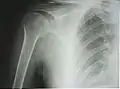

Рентгенограмма верхней части плечевой кости с выраженной хирургической шейкой

Проксимальный эпифиз представлен головкой плечевой кости (лат. caput humeri), отделённой от диафиза анатомической шейкой (лат. collum anatomicum). Головка сочленяется с суставной впадиной лопатки, образуя плечевой сустав. За шейкой располагаются два бугорка (апофиза) — больший и меньший (лат. tuberculum majus et minus), между которыми проходит межбугорковая бороздка — место сухожилия длинной головки двуглавой мышцы плеча. Ниже бугорков, на границе с диафизом, проходит хирургическая шейка (лат. collum chirurgicum) — место наиболее частых переломов плечевой кости[4].

К 4—6 годам указанные центры сливаются в единую головку плечевой кости. Замещение метаэпифизарного хряща на границе проксимального эпифиза и диафиза костной тканью (синостоз) наступает в подростковом возрасте, благодаря чему продолжается рост кости в длину. На рентгенограмме ребёнка или подростка определяется характерный светлый участок на месте метаэпифизарного хряща, который может быть принят за перелом или трещину[5].